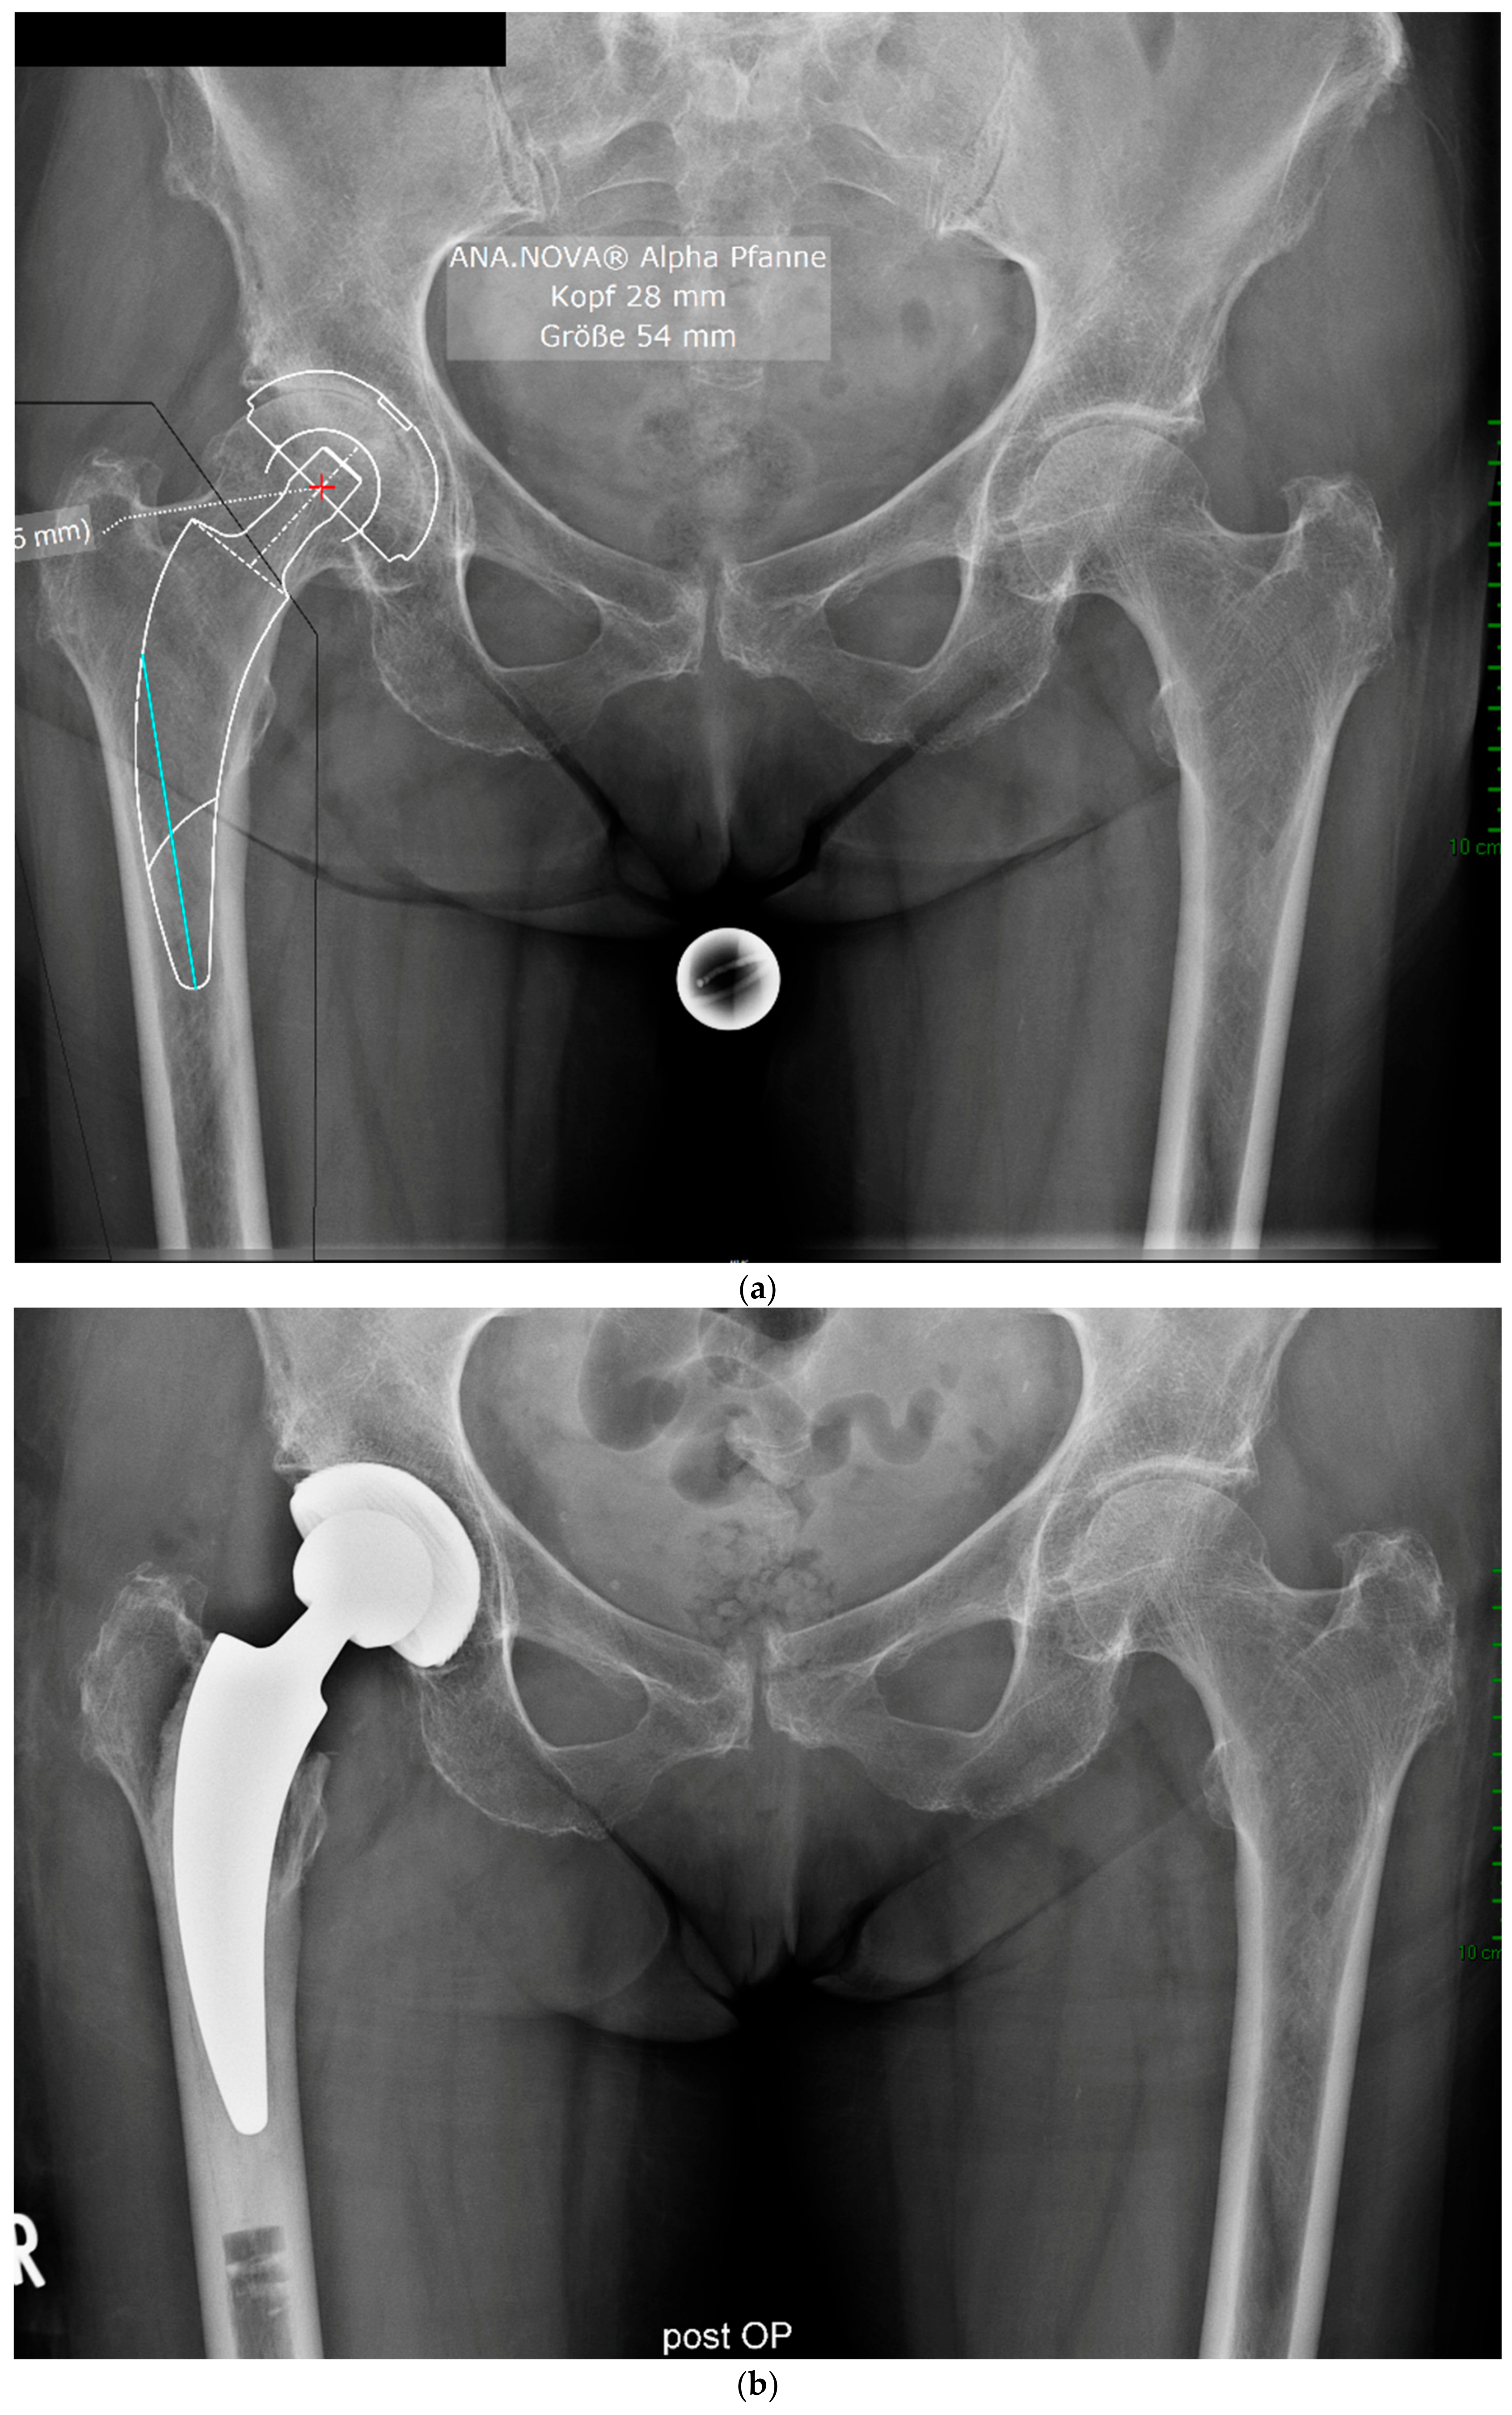

2. Materials and Methods